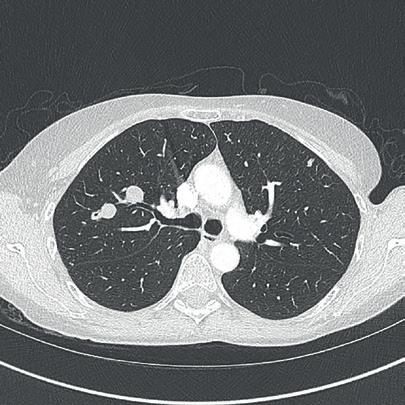

The incidence of lung cancer has increased considerably in the last few decades with the lung as the most common site of metastatic involvement. Despite the improvements in the diagnosis and treatment for malignant lung tumours, the prognosis of the patients is still unsatisfactory.1 Currently, locoregional chemotherapeutic techniques such as transpulmonary chemoembolization (TPCE) for the treatment of lung malignancies have gained increasing importance. The purpose of this retrospective study was to evaluate local tumour response and patient survival after the treatment of pulmonary metastases using TPCE as a palliative treatment method.

In TPCE, a 5 French (Fr) endovascular sheath and 5Fr headhunter catheter are routinely placed transfemorally under fluoroscopy until the pulmonary artery and subsequently the tumourfeeding segmental pulmonary branch are reached. A balloon catheter (up to 7mm in diameter) is optionally placed for better results.2 This selective pulmonary artery catheterisation results in a blockage of the arterial supply to the tumour tissue, resulting in regional ischaemic necrosis in the target tumour tissues while reducing damage to the surrounding normal lung parenchyma. Thereafter, mitomycin

and gemcitabine as chemotherapeutic agents are administered in combination with an embolization of lipiodol and microspheres. This extends the storage time of the injected cytostatics in the tumours and reduces the outflow into

the circulatory system.3 Consequently, the frequency and severity of systemic effects are limited. Other occlusion materials used are coils, polyvinyl alcohol, degradable starch microspheres, and gelatin sponges.

In our study, 223 patients (138 women, 85 men; mean age: 59.3±11.9 years) with unresectable lung metastases and/or not responding to systemic chemotherapy received repetitive TPCE (mean number of sessions 4.7±3.7) between January 1990 and May 2021. Patients had predominant lung metastases and in most cases with bilateral lung involvement. Origin of the metastases were either colorectal carcinoma (n=139) or breast cancer (n=84). Tumour-supplying vessels were catheterised selectively in order to apply chemotherapeutic agents locally, combined with lipiodol and microspheres. The response was assessed according to the revised RECIST criteria.

Of the evaluated 183 cases, partial response was achieved in 4.9% (n=9), stable disease in 62.3% (n=114), and progressive disease in 32.8% (n=60) of the patients. Mean and median overall survival time were 23.5 and 14 months, respectively.

TPCE can be used as a palliative treatment in unresectable lung malignancies to reduce the tumour burden or to achieve local tumour control,4 or as a neoadjuvant or curative treatment option combined with thermal ablation such as radiofrequency ablation (RFA) and microwave ablation (MWA) (Figure 1).5,6